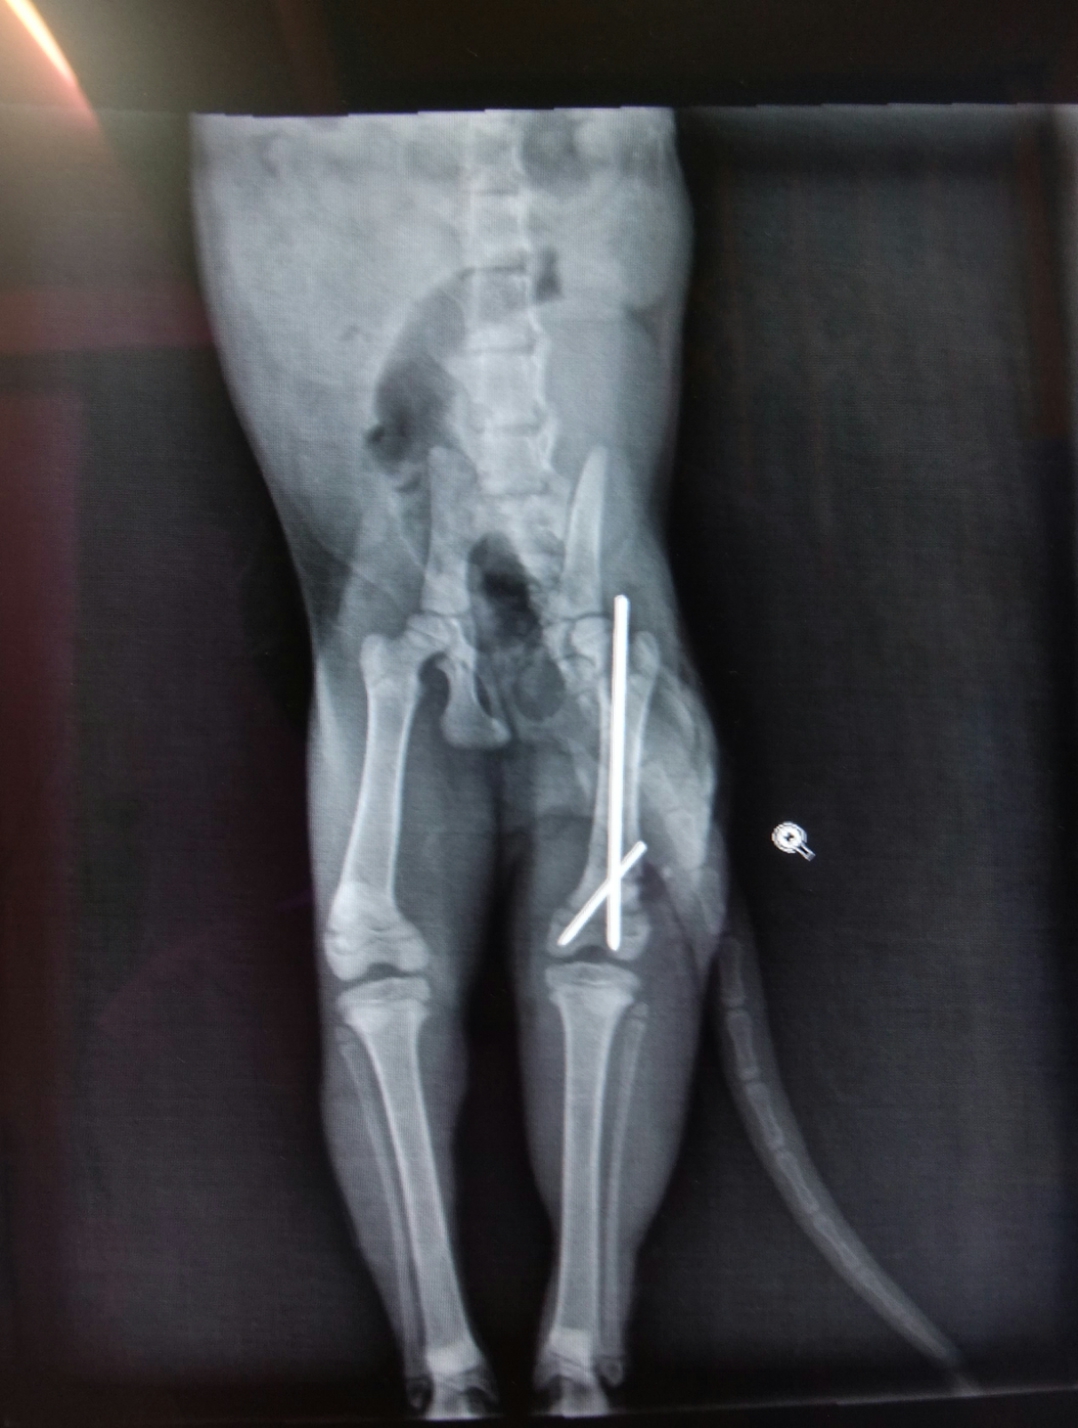

主題: 三個月小貓大腿粉碎性骨折癱軟在路中央險些被輾 申請者姓名: 康庭瑀 花色: 申請日期: 2013-11-27 18:07:58 申請者部落格: 申請者臉書網址: 所在縣市/合作醫院: 台南市/啄木鳥動物醫院 治療費用: 18950元 需求人數: 21人 已結案 (2014-01-10 17:50:13) 報名人員: Wendy x2(已付款)、Milkbau Lu(已付款)、vivian(已付款)、Jocelyne YuYu Kao(已付款)、臺北市支持流浪貓絕育計劃協會(代MD饅頭希望報名)(已付款)、蔡秀芳、小揚、王千枝 x2(已付款)、Cha-Mei Huang(已付款)、Bubu Wang(已付款)、林建華(已付款)、Wendy Tseng(已付款)、David Wei(已付款)、Crystal x4(已付款)、ERic YU(已付款)、林學凱(已付款)、chiawei x2(已付款)、 候補人員: 動物病情說明: 11/14下午約17:20左右,我要騎車去買東西,隱隱約約看到路中央有個白色東西,騎近一看,是隻小貓,車水馬龍,差點被車輾過!路上人車趕下班的趕下班,買東西的買東西,就是沒有人肯伸出援手拯救牠,就連把牠移到路邊也不肯。基於愛護流浪貓咪的精神,我馬上把他撈起來放在路邊,發現他不能走路,只能用爬的,且還有外傷,身體很臭,一身白毛染成灰黑色,且感覺很餓,不知道幾天沒吃東西了,又受傷又沒東西吃,貓是愛乾淨的動物,身體卻髒兮兮的,真的很可憐。於是我馬上送到附近的獸醫院,醫生說他大腿骨折了,但自家沒有儀器可檢查,需送至台南市區,於是我馬上帶小貓衝去市區先施打消炎針、照x光,發現一隻大腿粉碎性骨折,獸醫院說必須先住院觀察才能開刀,抽血檢查發現小貓肝指數很高,必須施以打針跟藥物治療,且白血球也很高,不排除傷口有感染的情況,還脫水,情況非常糟糕。於是當晚就住院了,由醫護人員悉心照料,第二、三次抽血檢查肝指數和白血球的情況有慢慢好轉了,但是脫水情況改善了,卻發現有貧血的問題,所以還另外驗了血型,開刀手術額外了輸血的步驟。開完刀後小貓就繼續住院,食慾體力恢復得很好,等拆完線就能出院了。 動物近況說明: 11/20開刀,用了骨釘,狀況良好,等拆線出院